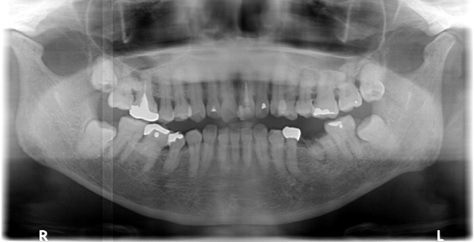

60代女性骨がなくGBRしインプラント2本埋入

治療前

治療後

施術名 | 右上2本インプラント埋入FGGBGBRソケットリフト その他はかぶせもの |

主訴 | 右上破折はれ |

施術の副作用(リスク) | 感染 |

施術の価格 | 1本GBR5万~10万(税抜き)+インプラント埋入補綴まで35万(税抜き) FGG5万 ソケットリフト6万 |

コメント | 右上は骨がなく抜歯の時にしっかり骨を作ってから埋入を行いました。またしっかりした歯茎も移植FGGしインプラントの予後をよくしました |